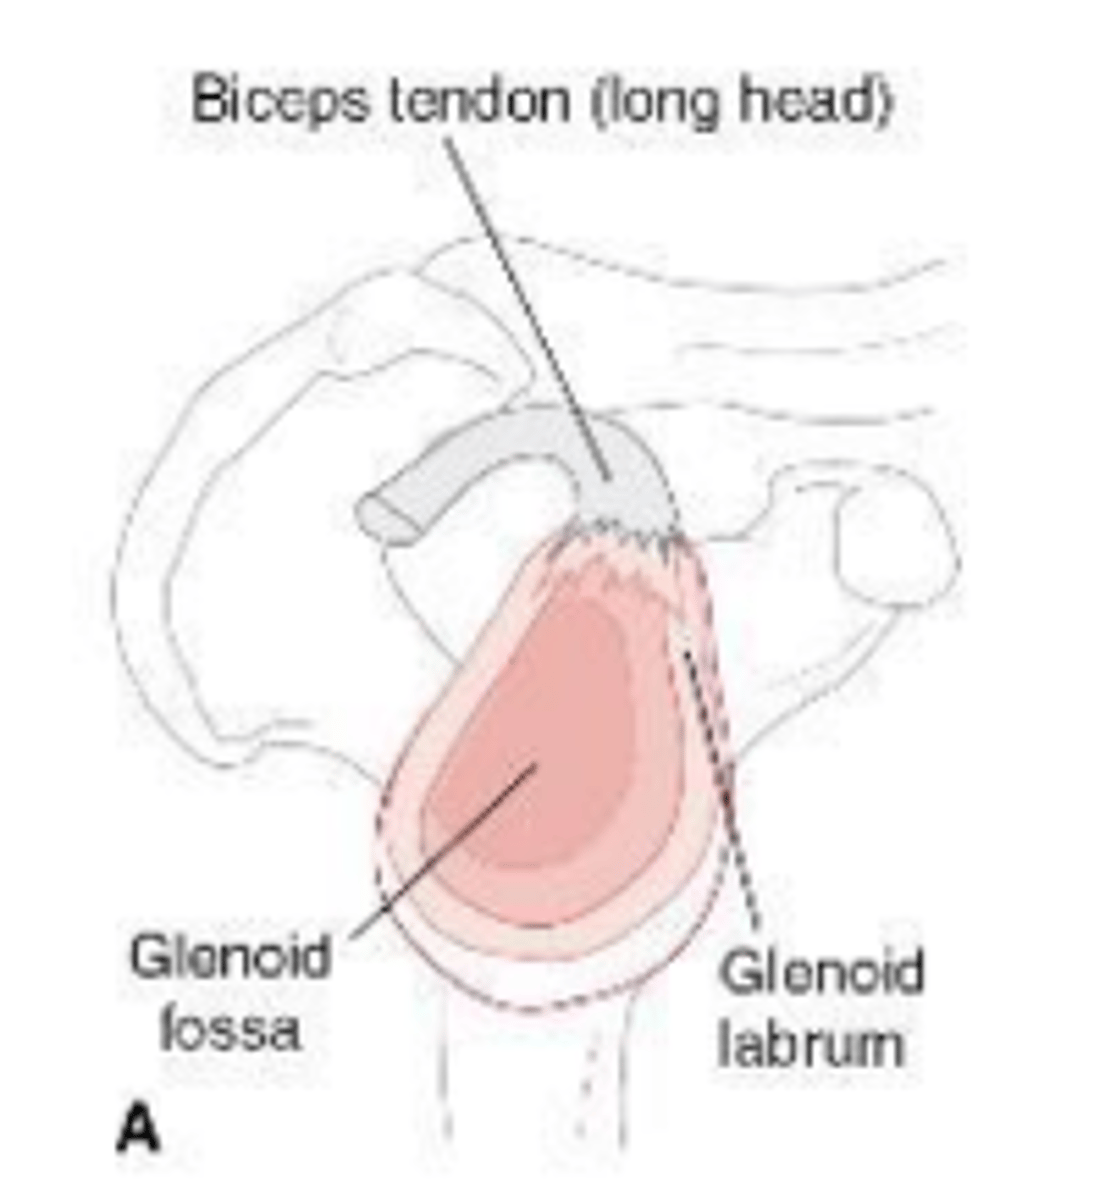

Normal superior and inferior glenoid labra without sub-labral leak of contrast material.

What does image A show?